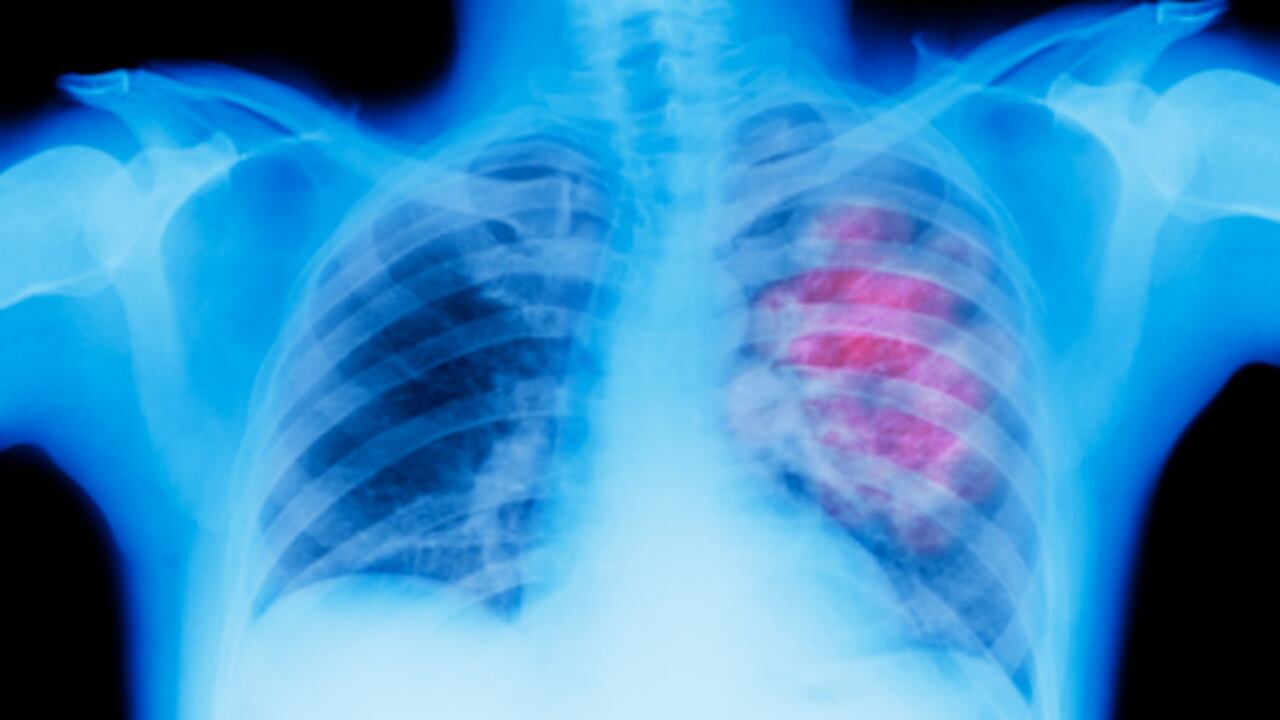

Existen más de 100 tipos de cáncer y por lo general suelen ser nombrados por su lugar de origen. La OMS indica que los más comunes son el de mama, pulmón, colorrectal, próstata, piel y gástrico.